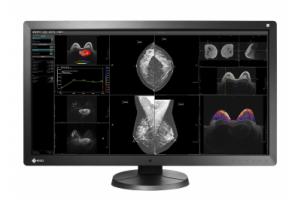

- Медицинские мониторы

Монохромный рентгенодиагностический ЖК-монитор с разрешением 3 мегапикселя.

Диагностический монитор LMD-DM30 предоставляет врачам четкое, яркое изображение с высокой степенью детализации. Монитор можно использовать в системах рентгенографии и других медицинских решениях, включая системы МРТ, КТ, системы компьютерной рентгенографии, прямой цифровой рентгенографии и цифровой маммографии.

Этот медицинский монитор отображает равномерное и стабильное изображение с высоким разрешением, а также обладает превосходной яркостью и контрастностью.

Полезный размер экрана по диагонали составляет 20,8 дюйма (52,8 см). При этом монитор оснащен ЖК-экраном с высоким стандартным разрешением 1536 x 2048 (3 мегапикселей).

Это первое поколение диагностических мониторов Sony, в которых реализована технология ISD (независимое субпиксельное управление). При использовании технологии ISD эффективное горизонтальное разрешение увеличивается втрое, до 9 мегасубпикселей (1536 x 6144), что дает врачам возможность просматривать самые мелкие детали и на основании этого ставить точный диагноз.